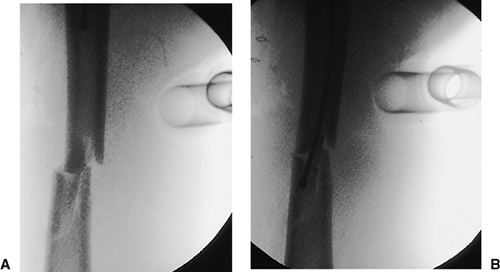

Figure 21.47.

Distal fixation. Correct rotational alignment of the fracture should be confirmed before distal fixation. The c-arm should be positioned to obtain an optimal lateral view of the distal end of the nail. The goal is to pass the beam exactly in-line with the axis of the screw holes (A). This position has been obtained when the holes appear perfectly round (B). An elliptical appearance of the holes suggests mal-alignment of the beam. |